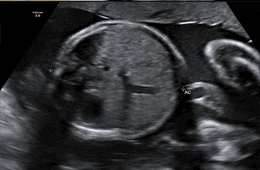

One of the main aims of routine antenatal care is to identify babies who are not thriving in the womb. It is possible that medical interventions might improve outcomes for these babies, if they can be identified. Doppler ultrasound uses sound waves to detect the movement of blood in vessels. It is used in pregnancy to studyblood circulation in the baby, uterus and placenta. Using it in high-risk pregnancies, where there is concern about the baby's condition, shows benefits.

Uterine arteries are the vessels which carry blood to your womb (uterus). A uterine artery Doppler scan checks that enough blood is reaching your placenta.

Your baby needs plenty of nutrients and oxygen to grow at a healthy rate. Therefore, the walls of your uterine arteries should be stretchy, to allow as much blood through as possible. In pregnancy, these normally small arteries increase in size to allow more blood to reach your womb easily.

If blood can’t get through to the placenta easily enough, your baby may not get the nutrients and oxygen he needs via the umbilical cord.